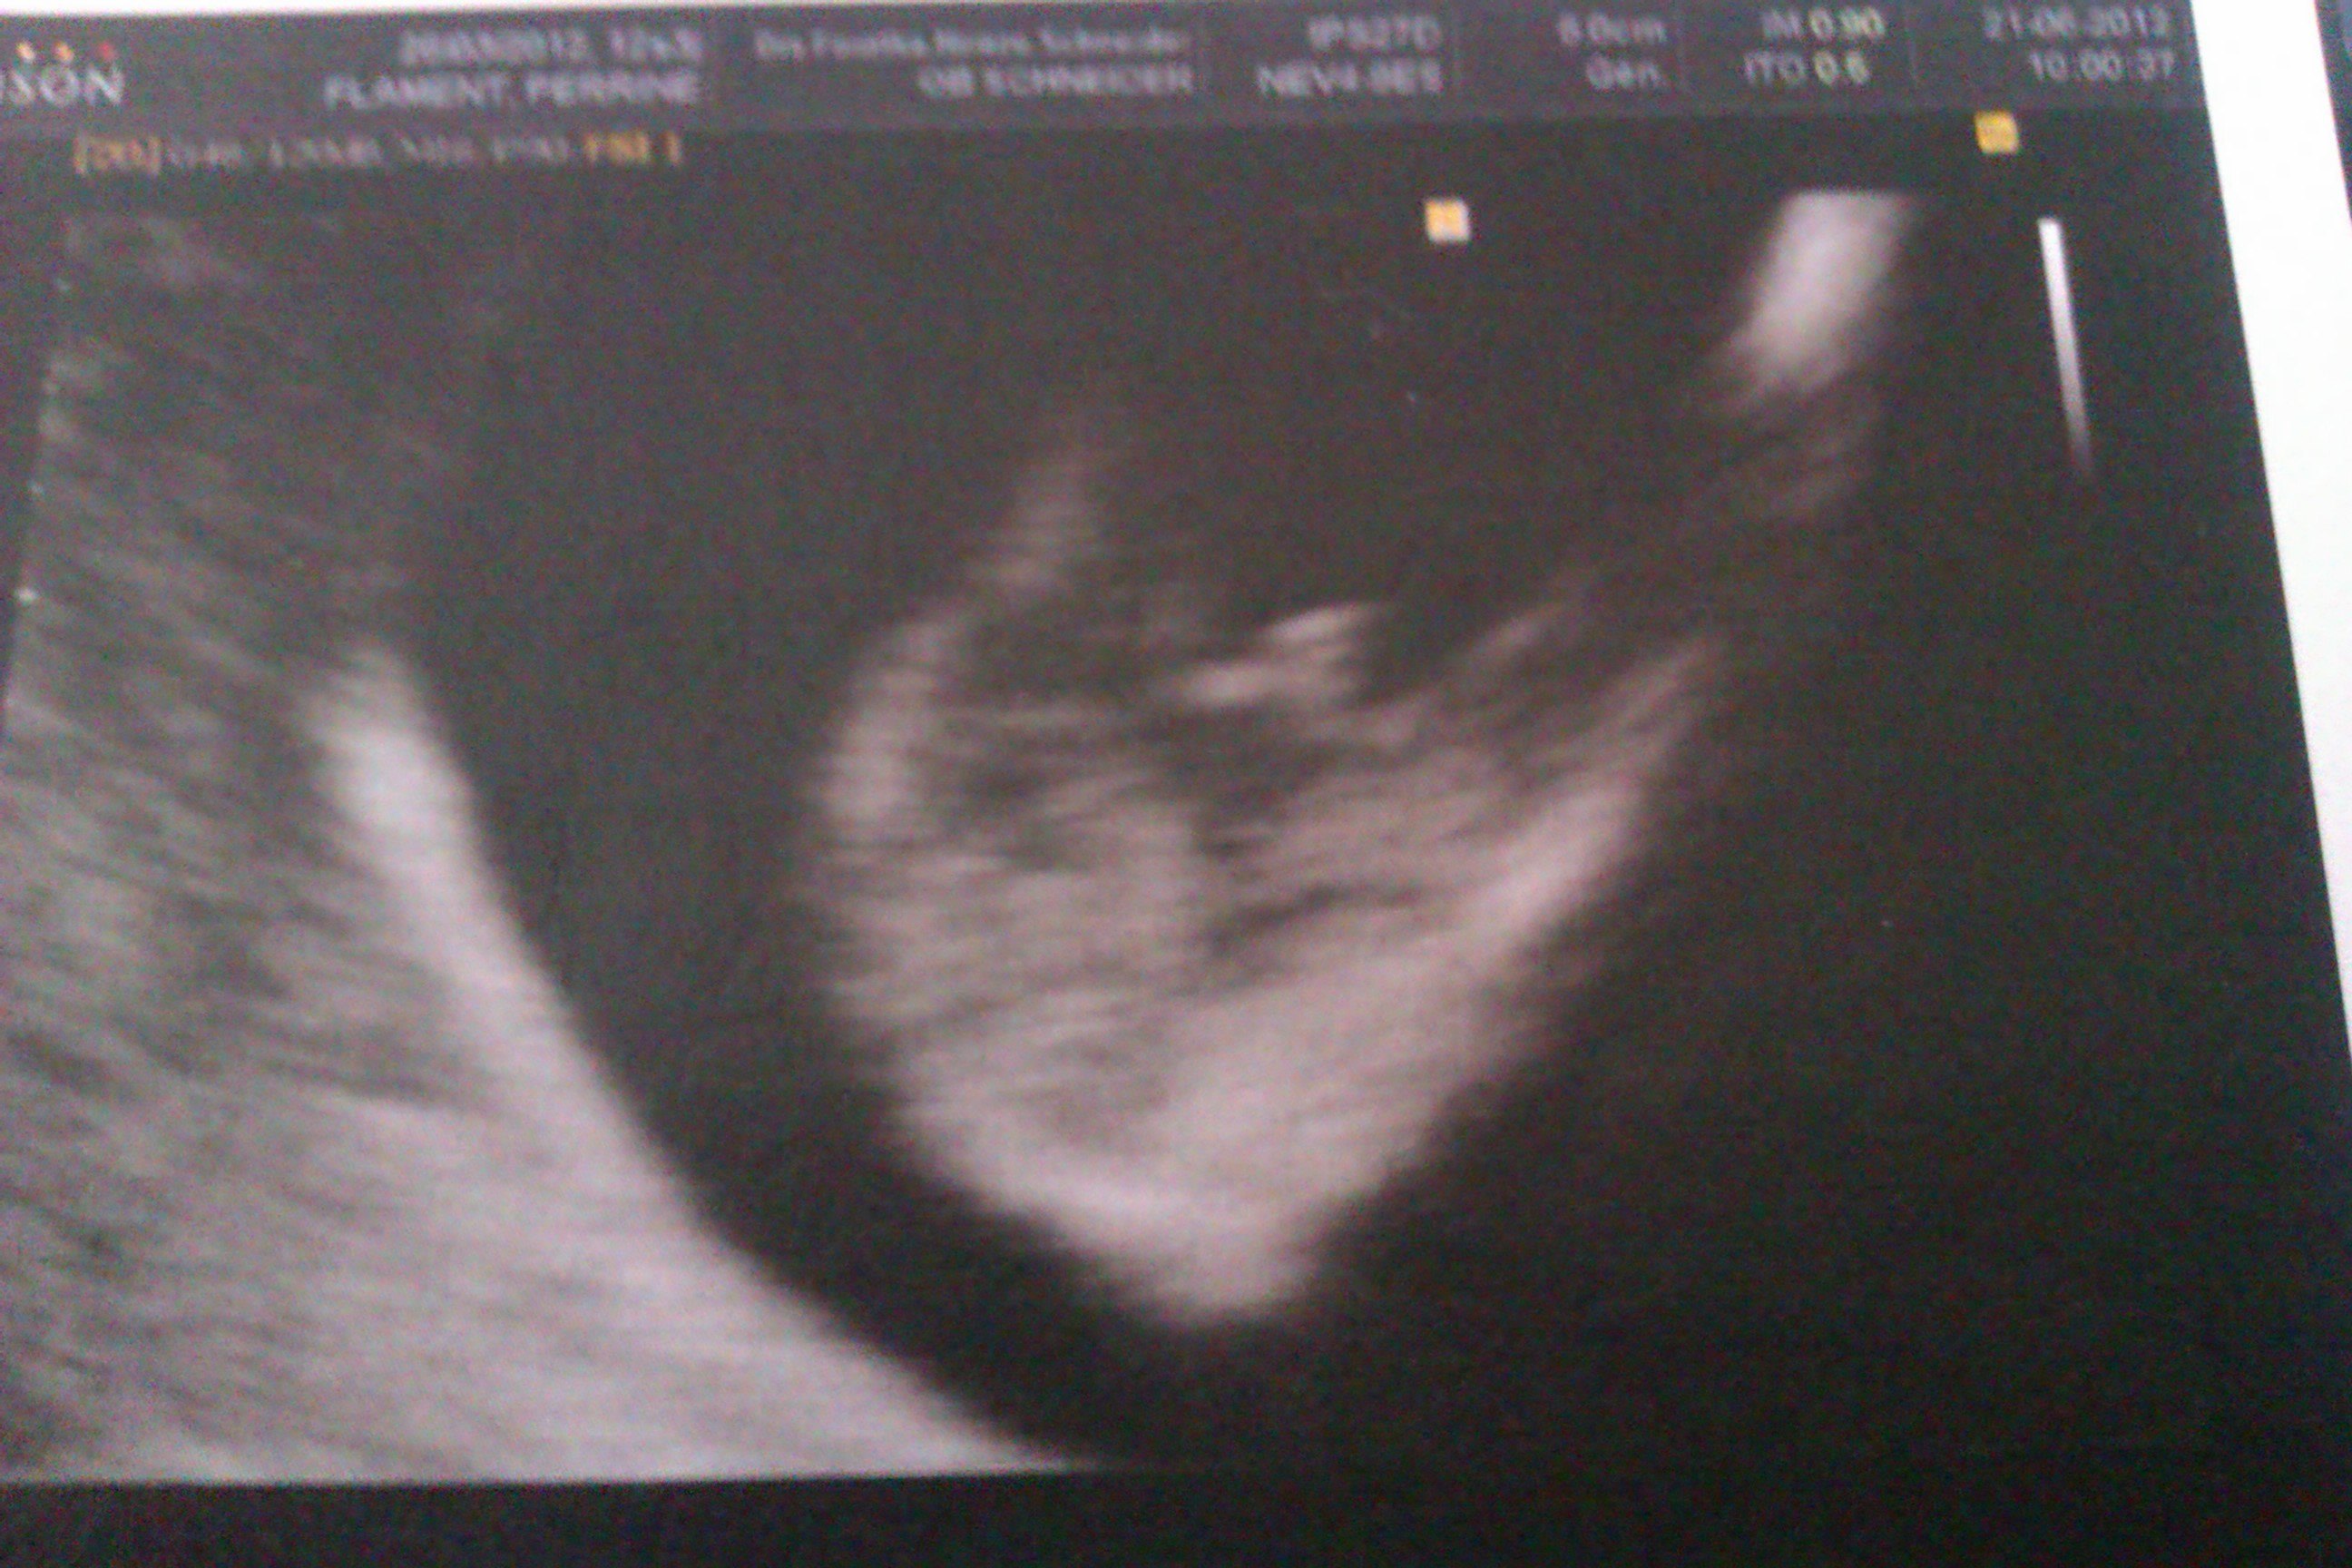

Voila les photos, la première ce sont ses fesses avec selon lui le zizi et les testicules